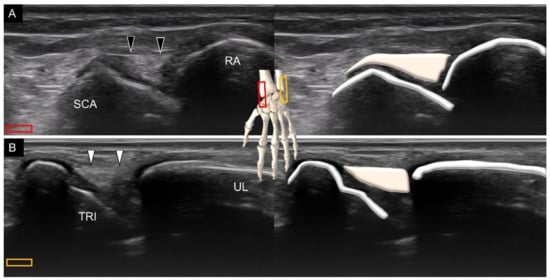

2. Sonoanatomy of Carpal Bones

3.1. Attachment to the Capitate

6. Sonoanatomy of Dorsal Intrinsic Carpal Ligaments

7. Sonoanatomy of Wrist Collateral Ligaments